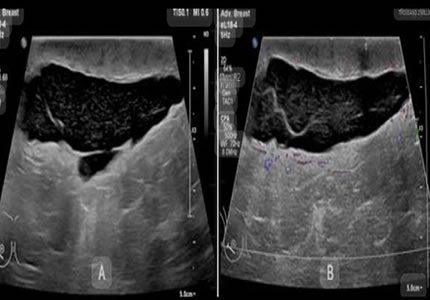

Comprehensive pelvic ultrasound evaluations for a wide range of non-pregnancy female health concerns, symptoms, or referrals.

Routine & Diagnostic Gynaecological Scans